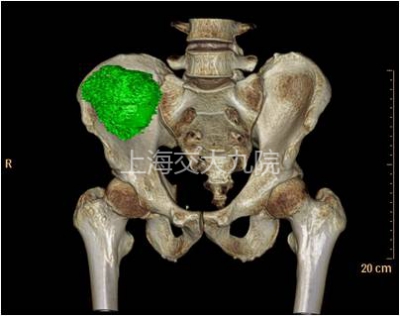

图1 术前MRI显示右髂骨软骨肉瘤,3D重建肿瘤边界,骶髂关节不能保留